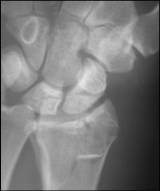

The following fracture is

best described as…

1. Transverse

2. Oblique

3. Comminuted

4. Incomplete